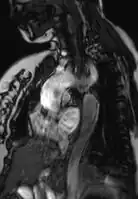

Coarctation of the aorta can be accurately diagnosed with magnetic resonance angiography. In teenagers and adults echocardiograms may not be conclusive.

The severity of coarctation of the aorta can be rated by a combination of the smallest aortic cross-sectional area of the aorta (adjusted for body surface area) as measured by 3D-rendered contrast MRI, as well as mean heart rate–corrected flow deceleration in the descending aorta as measured by phase contrast magnetic resonance imaging.[9]